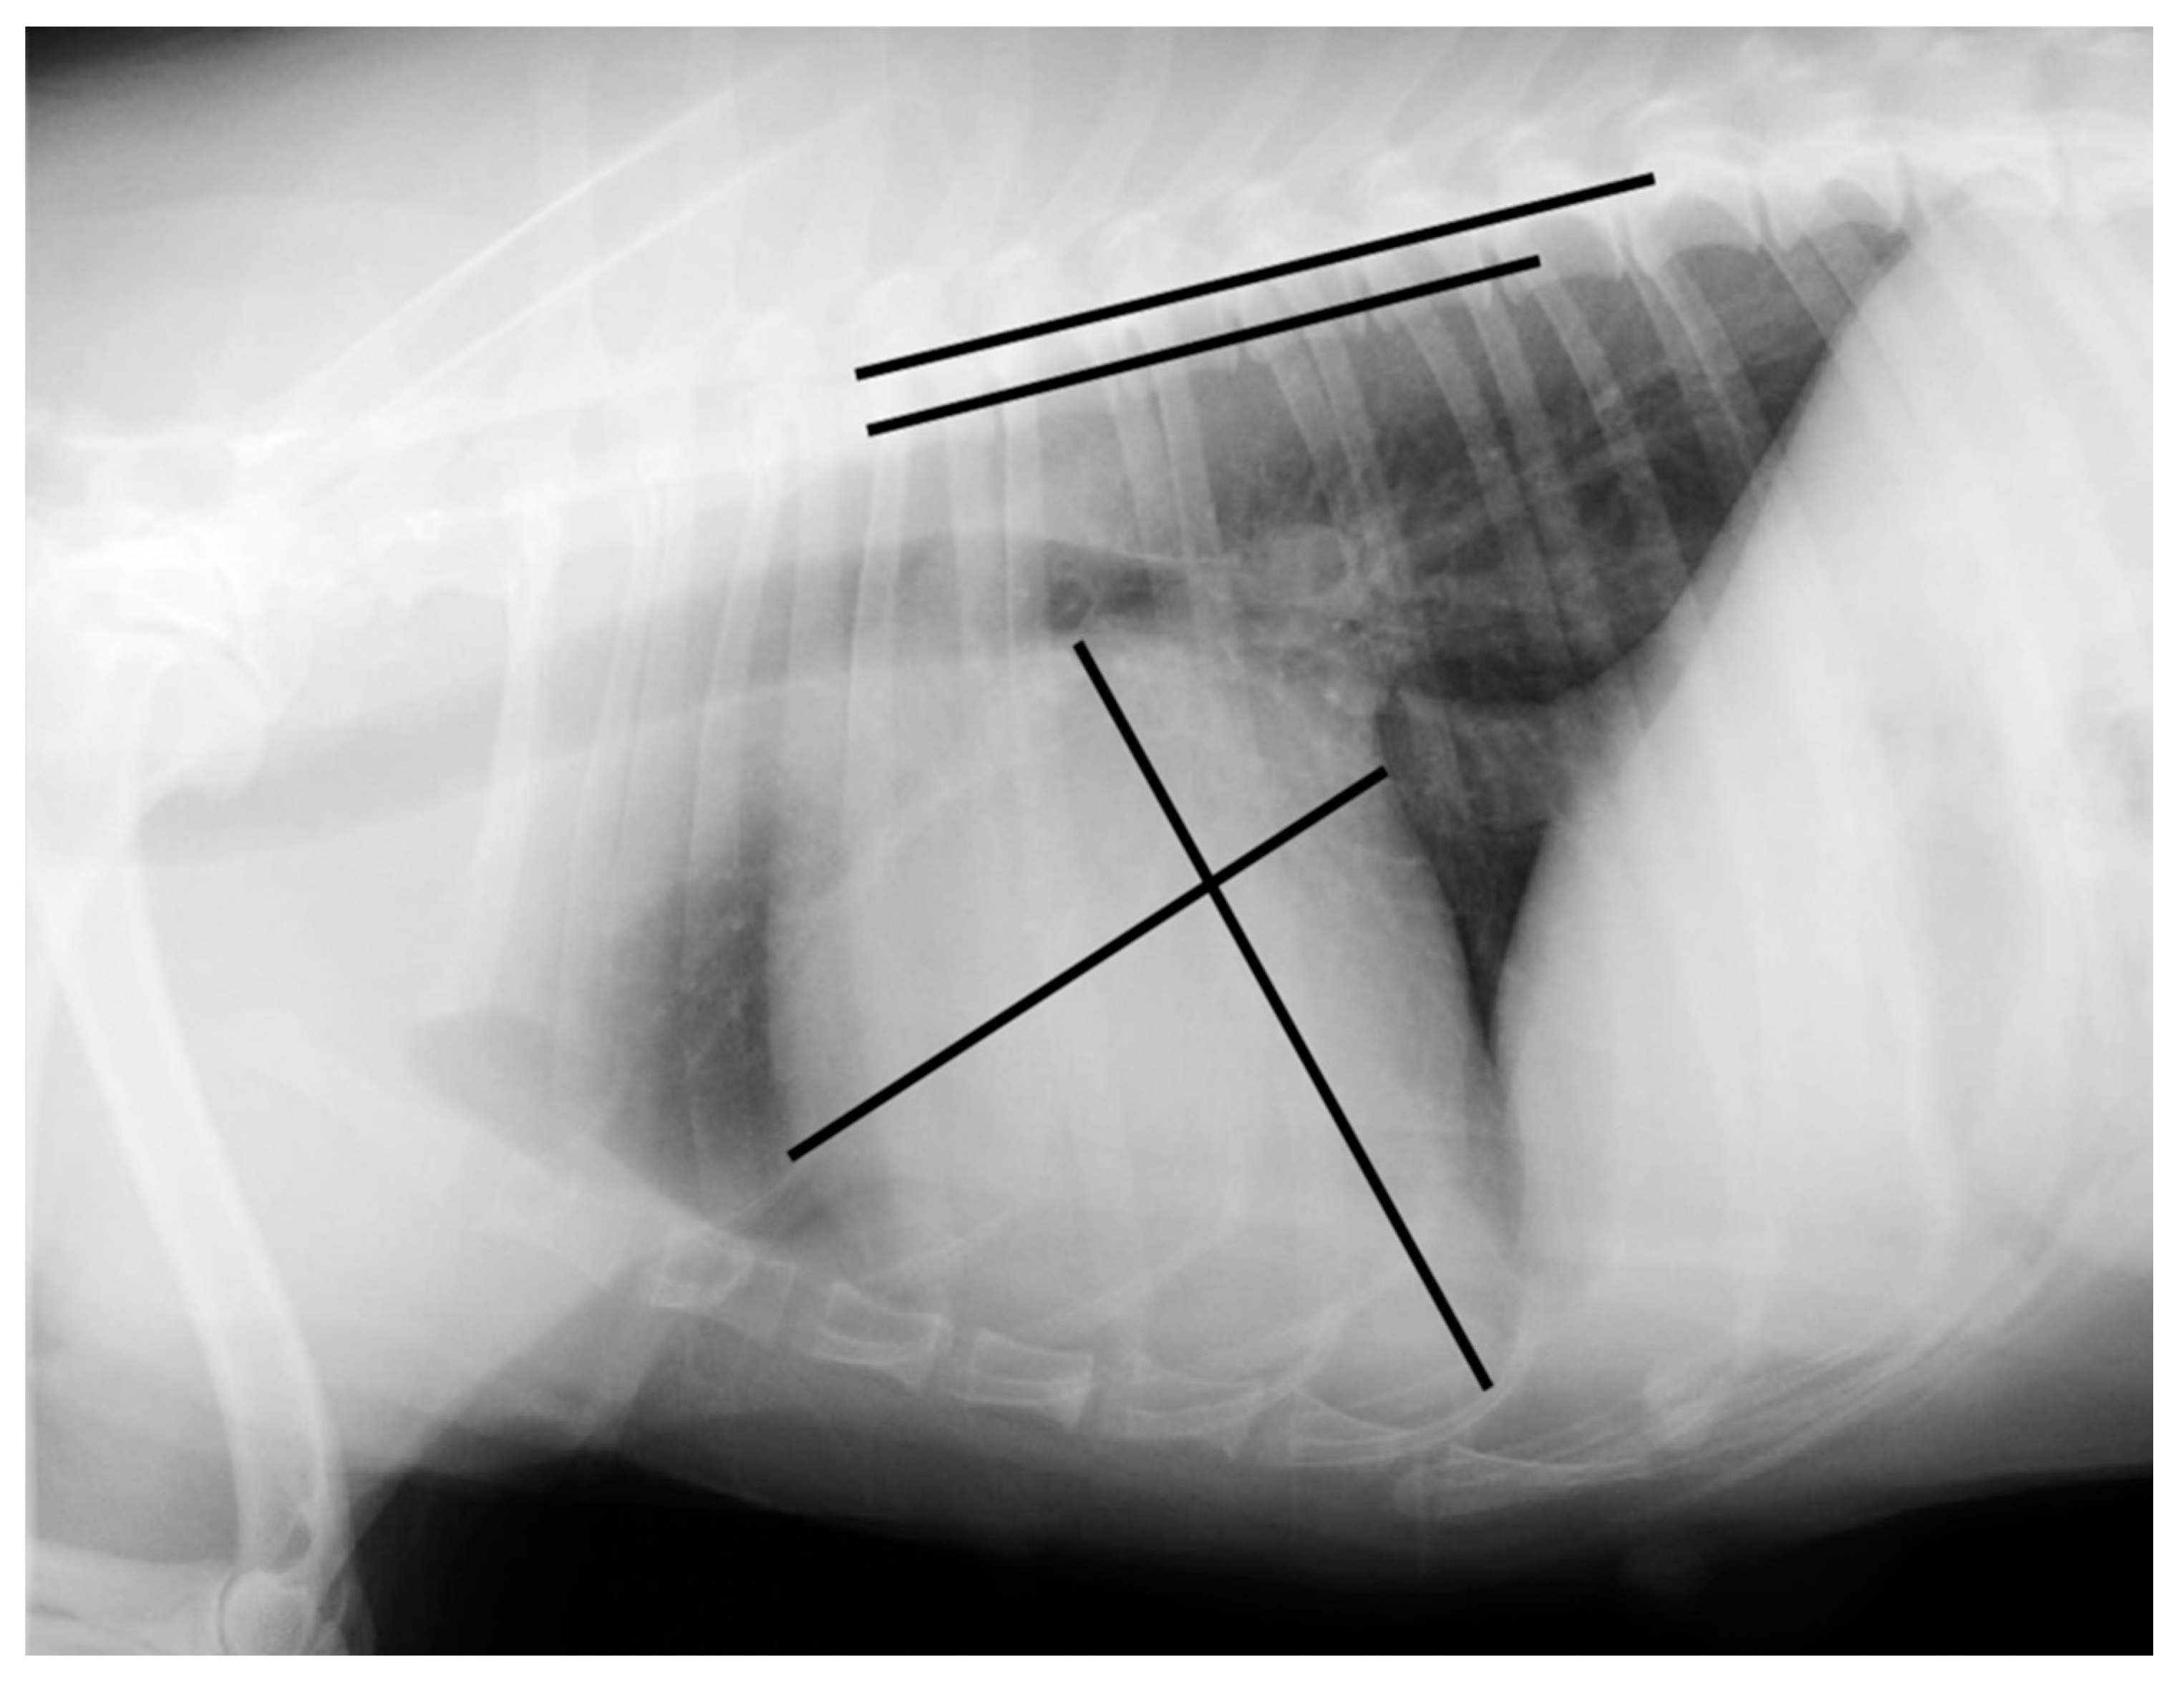

Measurements were made using an adjustable calliper in millimetres, which was then converted to vertebral units (v) exact to 0.1 v, according to the method described by Buchanan and Bucheler [4]. All of the measurements were performed by the same examiner (EC) using DICOM PACS view radiography computer software (Synapse, Fuji, Tokyo, Japan). In the right lateral radiograph, the long axis of the heart was measured from the ventral border of the left main stem bronchus to the most distant contour of the cardiac apex (L). The maximal short-axis of the heart was measured perpendicular to the long-axis (S). The two measures were repositioned over thoracic vertebrae beginning with the cranial edge of T4, using an adjustable calliper (Figure 1 and Figure 2).

Figure 2. Right lateral radiograph illustrating an example of a vertebral heart scale calculation in a Brittany Spaniel suffering from a myxomatous mitral valve disease with a vertebral heart scale of 11.6 v (the image was acquired using a PICKER CONVIX 80–UNIVERSIX 120 device (Picker International, Uniontown, OH, USA); the kVp, mA, and time settings were not recorded). Two lines are drawn on the heart to measure its long and short axes. They are then transposed onto the spine and recorded as the number of vertebrae beginning with the cranial edge of T4. These values are estimated to one decimal place and added to obtain the vertebral heart size.